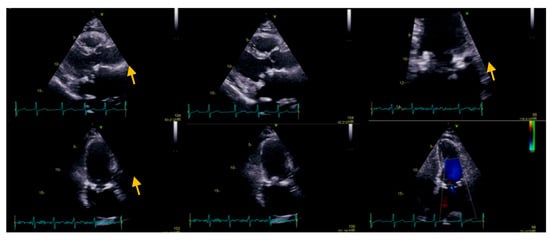

:1. Case Presentation